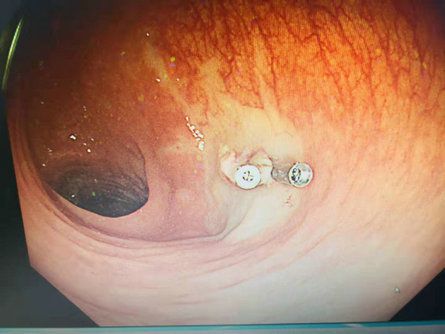

今年以来,我院消化内科积极开展新技术、新项目。5月25日,消化内科主任、副主任医师李红钊和科室内镜医师团队为68岁患者独立实施了内镜下粘膜切除术(EMR)。患者高某,女,以“慢性便秘”收住院。入院后行结肠镜检查提示:降结肠息肉,大小0.5cmx0.4cm,扁平状,(病理腺瘤样息肉)。直肠息肉,大小0.8cmx1.0cm,表面呈分叶状,有亚蒂(病理绒毛管状腺瘤)。在术前充分讨论的基础上,与患者及家属积极沟通同意后,给予降结肠息肉APC治疗术和直肠息肉EMR治疗术,术后完整病理提示:管状绒毛状腺瘤伴腺上皮轻一中度异型增生。此项技术目前在我院己完成3例,均康复出院,填补了我院消化内镜介入治疗新技术--内镜下粘膜切除术(EMR)治疗领域的技术空白。

随着内镜操作技术的改进和镜下治疗新技术的不断开发,消化道息肉治疗的技术越来越成熟,目前内镜下息肉切除方法有:高频电切除、微波、射频、氩离子激光等。内镜下消化道息肉切除治疗的意义在于可全瘤活检,明确息肉性质,治疗出血,切除癌前病变,预防癌的发生。与传统剖腹手术相比,内镜下治疗费用低、不需麻醉、损伤小、痛苦少、术后恢复快、并发症及死亡率低等优点,对年老体弱及婴幼儿也适用,目前已被广泛接受,替代剖腹手术成为消化道息肉治疗的首选方法。内镜下粘膜切除术(EMR)是指在内镜直视下将病变粘膜进行局部切除,该切除方法只涉及黏膜层及部分黏膜下层,不涉及固有肌层。此前,该项目多在三级医院开展,我院消化内科该技术的顺利开展,将为全县广大人民群众带来新的福音,也为我院消化内科技术提升寞定了新的基础。